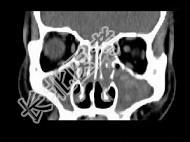

- 单项选择题男,14岁, 持续性鼻塞、嗅觉减退,流脓涕数年, CT检查如图,最可能的诊断为 ( )

A、鼻炎及鼻窦炎

B、鼻及鼻窦息肉

C、过敏性鼻炎及鼻窦炎

D、恶性肉芽肿

E、上颌窦癌